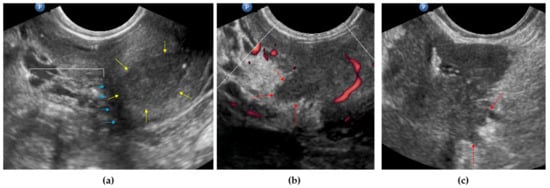

2.3.1. Endovaginal/Transrectal Ultrasonography

3.4. Mesometrial LNs

4.5. Vaginal Wall/Fornix Infiltration